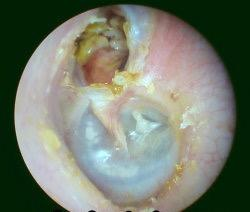

Chronic Suppurative Otitis Media (CSOM)

A 17-year-old boy presented with a long history of scanty, foul-smelling discharge associated with on/off bleeding from the ear. Endoscopic findings are shown.

Type of Perforation

- Perforation in Pars Flaccida, attic perforation, indicating unsafe CSOM.

Treatment

- Water precaution, aural toilet, topical APX.

- For unsafe CSOM: Surgery (Tympanoplasty + mastoidectomy).